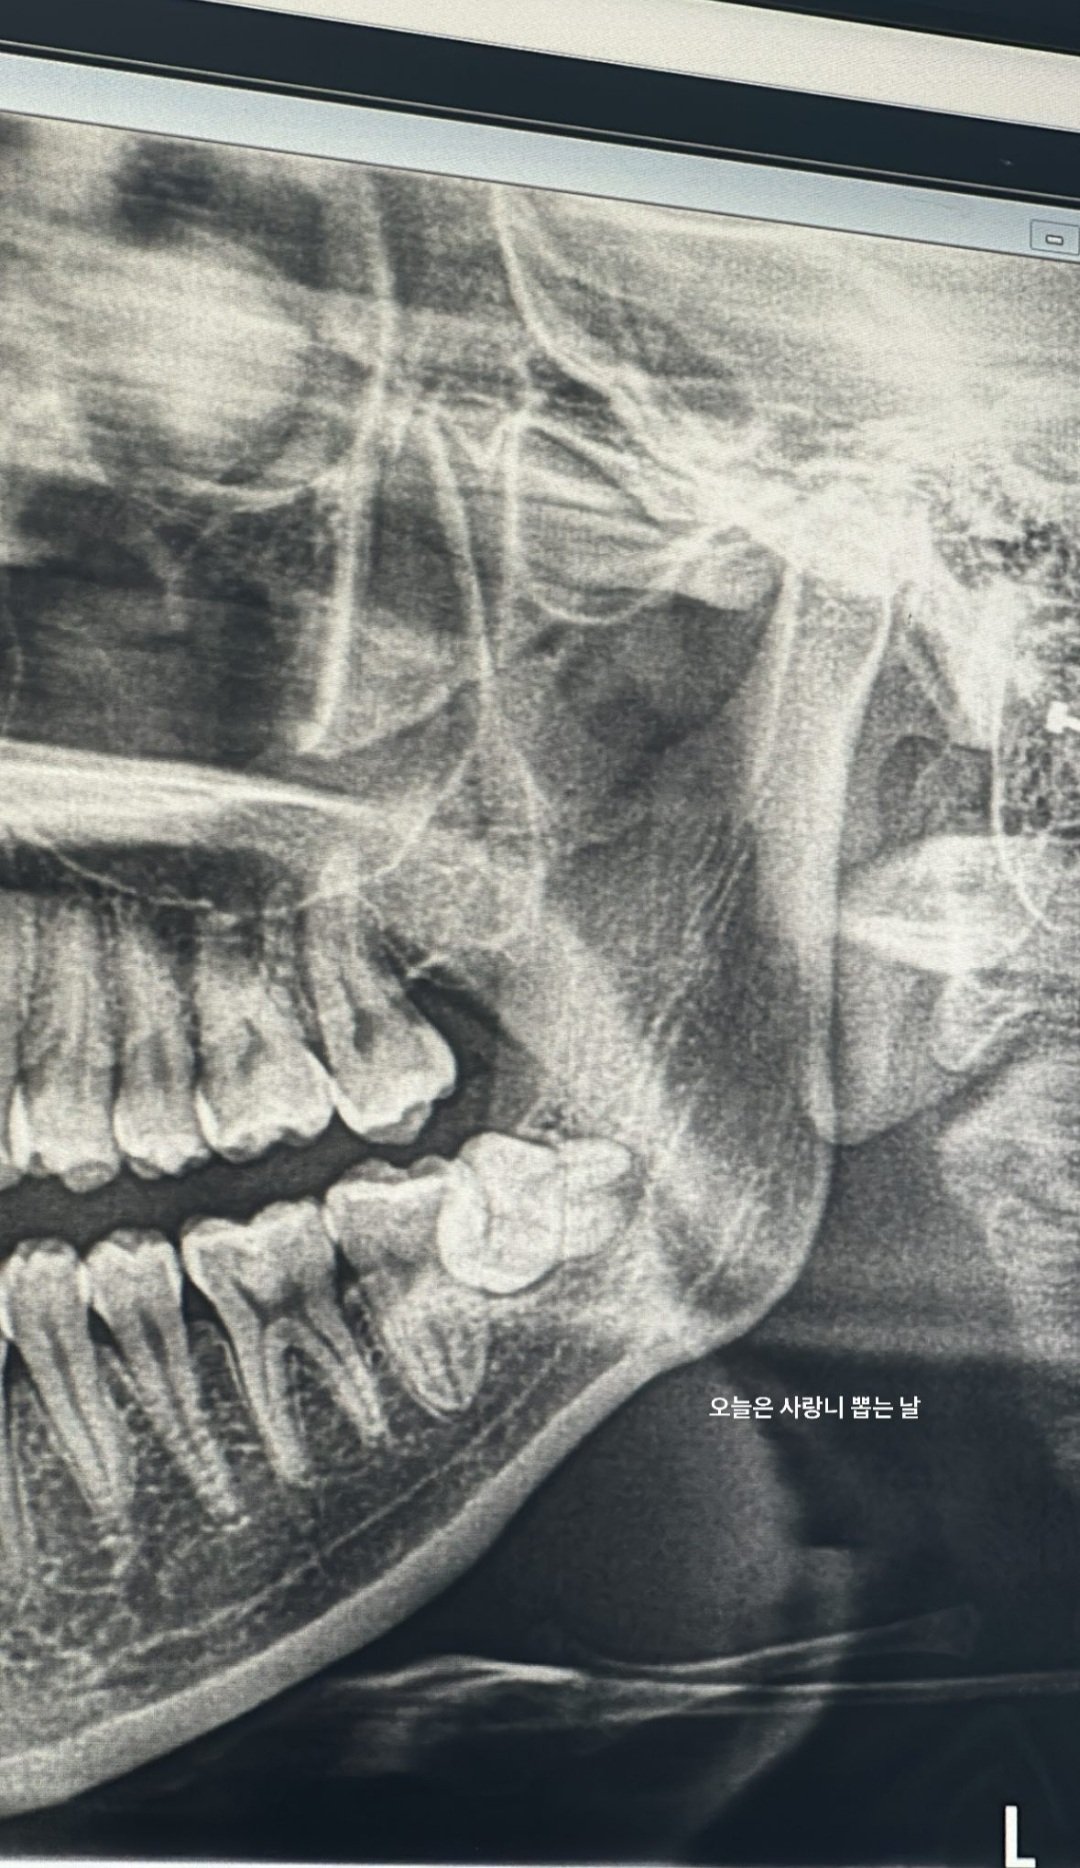

Pe data de 24 octombrie, Rosé din BLACKPINK a anunțat prin intermediul contului său personal de Integram faptul că va suferi o intervenție chirurgicală stomatologică de extragere a măselei de minte. La doar o oră de la anunțarea acestui lucru, artista a postat o fotografie și un scurt videoclip cu aceasta de după intervenție.

Procedura de extracție a măselei de minte este în prezent o intervenție chirurgicală orală realizată frecvent în clinicile stomatologice. Procedura nu durează mult, nu prezintă riscuri mari și se face cu anestezie locală.